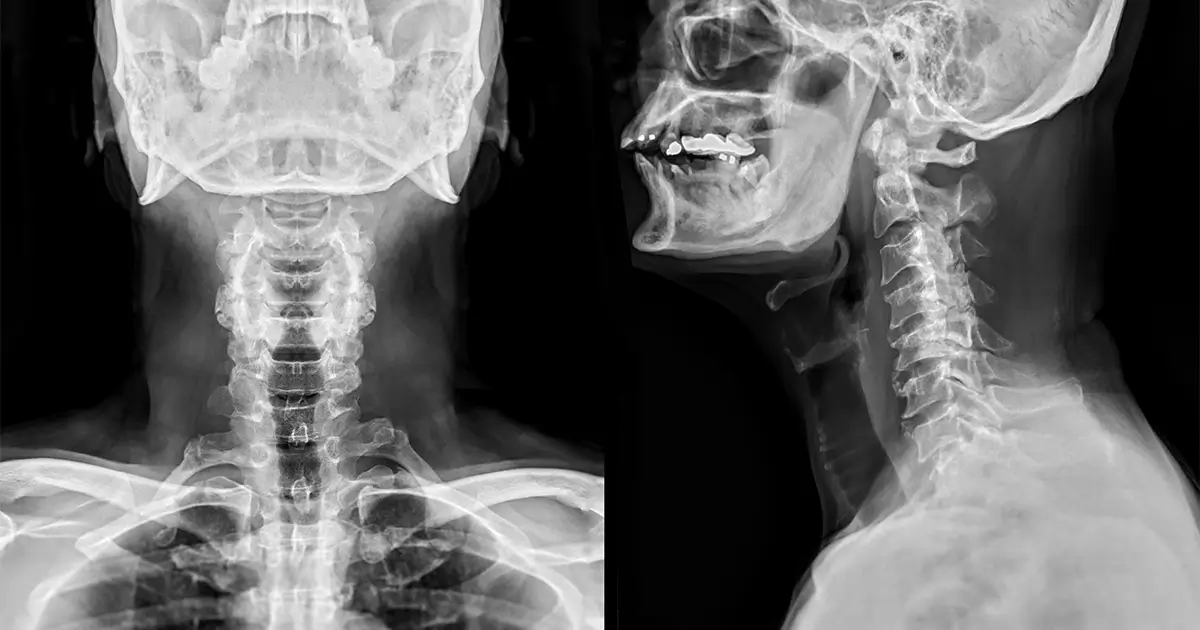

Spinal cord injuries in Fort Lauderdale, Florida, are classified into four main types: cervical, thoracic, lumbar, and sacral. Each type corresponds to a specific section of the spinal column, composed of rings of bone called vertebrae. The location of the injury along the spinal column dramatically influences the level of dysfunction experienced by the individual.

The cervical vertebrae are located in the neck region. Injuries in this area often result in loss of function in both the arms and legs, a condition known as tetraplegia or quadriplegia. These injuries can also cause spinal cord paralysis, significantly impacting the victim’s mobility and quality of life.

The thoracic vertebrae are in the chest area. Injuries here typically affect the chest and legs, leading to paraplegia. This means the individual loses the ability to move and feel in the lower part of the body, including the legs.

Lumbar vertebrae are found in the lower back. Injuries to this part of the spine generally result in some loss of function in the hips and legs. Similarly, sacral vertebrae, located from the pelvis to the end of the spinal column, can also cause loss of function in the hips and legs when injured.